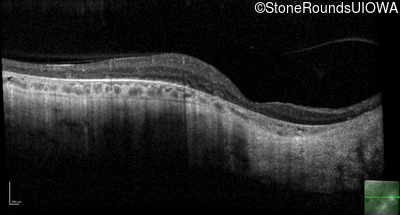

Optical Coherence Tomography - Left - 20/40 sc

Exemplar / OCT Stack

OCT Stack